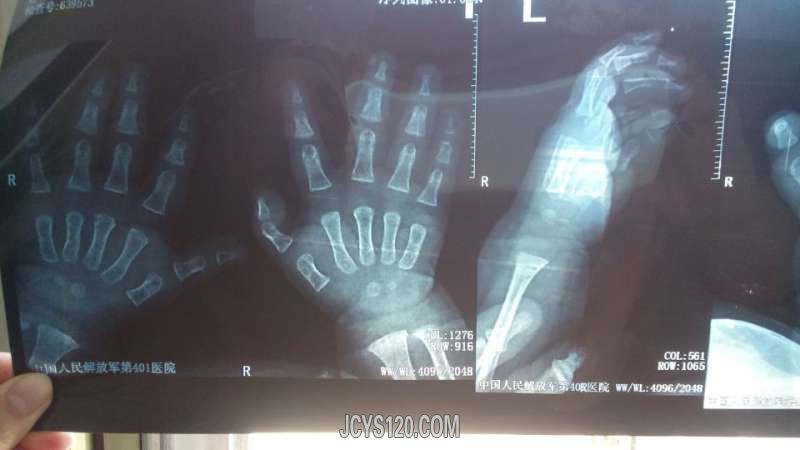

• 突然右侧大拇指弯曲半小时 attach_img agree

• 不爱数学爱几何 2015-5-12

• 一般情况:小患儿男性 9个月 主诉:其母主诉突然小儿大拇指弯曲半小时 现病史:小患者于半小时前午睡起来哭闹,其母亲抱着无意间发现小患者大拇指伸不直,弯曲,其母亲说睡觉前小患者一直被母亲看护,没有外伤史, ...  阅读全文>